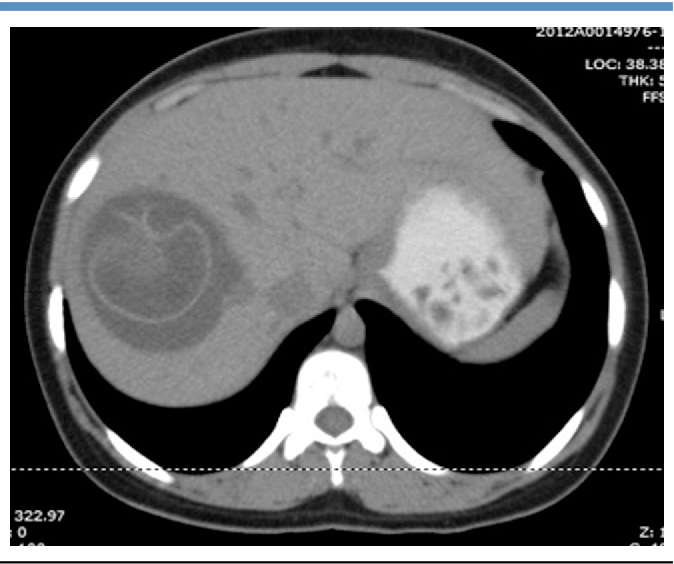

Daughter cysts

Echinococcal cyst within a larger cyst

Can occur in liver or spleen